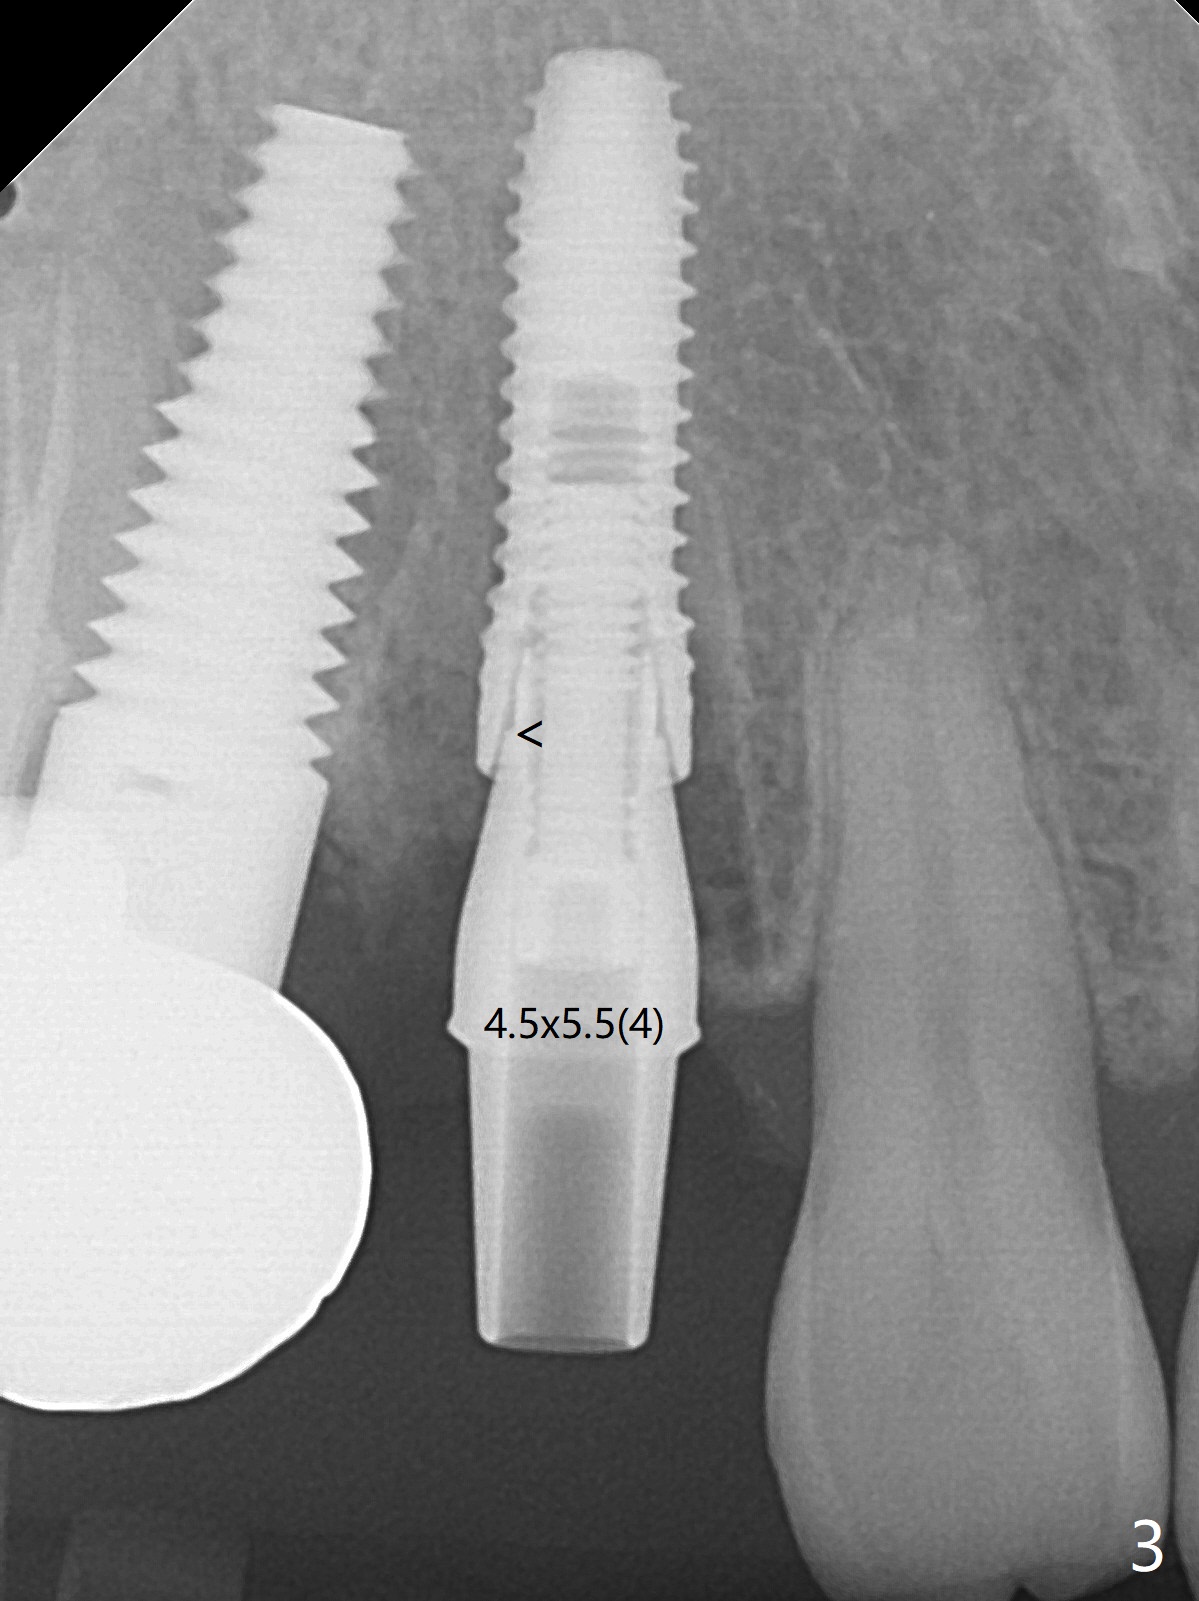

When the recemented crown at #6 is removed, the post is found to have been fractured. When the tooth is extracted, the socket walls are found intact. After moving the initial osteotomy (Fig.1) mesial, a 3.8x13 mm implant is placed (Fig.2). Clinically it appears supracrestal lingually. So the implant is placed deeper, but a cemented abutment is incompletely seated (Fig.3 <). When a longer abutment is used (easy grasping), it is seated completely (Fig.4). Then sticky bone is packed (Fig.5 *). When an immediate provisional is fabricated and seated, PRF membranes are inserted into the remaining gap between the gingiva and the provisional. Free hand surgery takes time and more intraop X-ray. It is inconvenient with nervous patients. The socket heals 2 weeks postop (Fig.6). The provisional will be next relined and reseated. It is difficult to insert gingival retraction cord 3.5 months postop because of the deep mesial margin. When an abutment with longer cuff is placed, the packing is easier (no biologic width violation, Fig.7 (^: resorbed mesial crest), as compared to Fig.5). When the crown is cemented (un-esthetic due to failure of use of temporary abutment), the metal shows at #5 with gingival recession because of buccal placement (Fig.8-10). Bone resorption is severe between #5 and 6 (Fig.7), as related to large gingival embrasure (Fig.9 *). When #5 crow is redone, move the gingival margin apical and fabricate provisional.